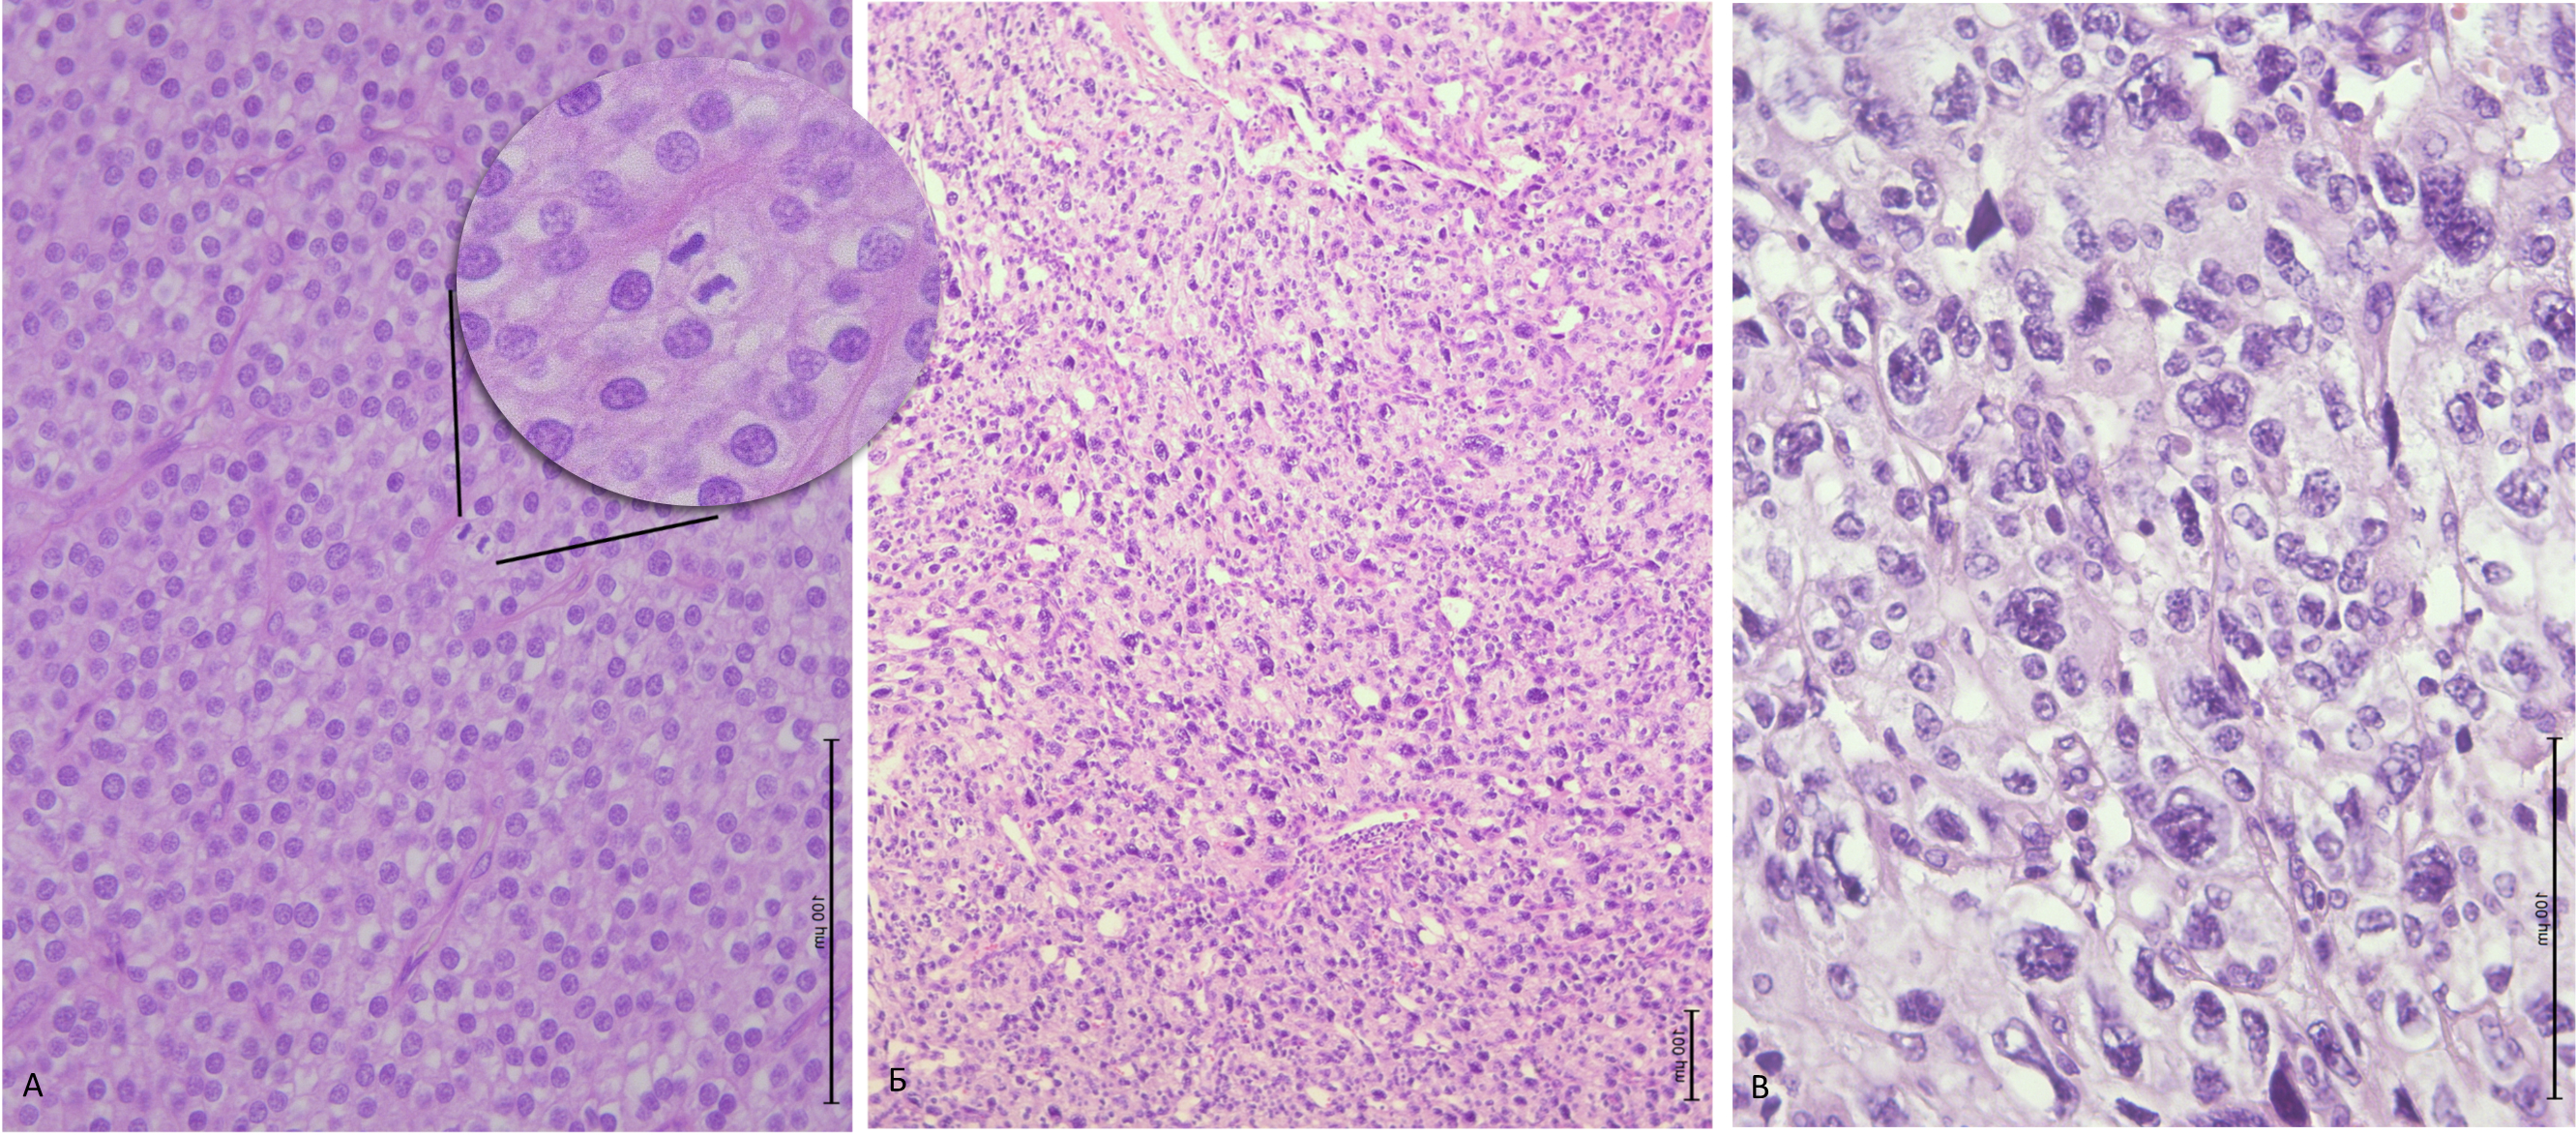

- Оценка морфологических характеристик опухолей. Морфологические характеристики различных новообразований ОЩЖ представлены в табл. 3 (рис. 3–5).

С учетом поправки Бонферрони p0 = 0,0056 были выявлены различия по частоте ядерной атипии. При попарном сравнении частота ядерной атипии выше в группе карцином (p < 0,001; χ2) и атипических аденом (p < 0,001; χ2), чем в группе аденом ОЩЖ.

Рис. 3. Рак ОЩЖ: А — широкие фиброзные тяжи; Б — инвазия капсулы опухоли; В — повышенная митотическая активность карциномы ОЩЖ (3 митоза в 1 РПЗ); Г — прорастание рака ОЩЖ (1) в ткань щитовидной железы (2)

Широкие фиброзные тяжи — один из подозрительных в отношении карциномы признаков, однако важно помнить, что они также могут встречаться у пациентов с МЭН1 и МЭН4, при вторичном гиперпаратиреозе, в крупных и «старых» аденомах с дегенеративными изменениями [3, 18, 19]. В нашей работе этот морфологический критерий был выявлен в 82% карцином, что согласуется с данными литературы [22, 25] (см. рис. 3). Они также присутствовали и в атипических аденомах (78%) без значимой разницы с группой карцином (р = 0,538).

Доля карцином, демонстрирующих ядерную атипию в нашем исследовании, составила 43%, что соответствует литературным источникам [20, 25]. Следует отметить, что очаговая ядерная атипия, может встречаться в аденомах в рамках так называемой эндокринной атипии. По нашим данным частота ядерной атипии статистически значимо больше в карциномах и атипических аденомах по сравнению с группой доброкачественных аденом (р < 0,001 с учетом поправки Бонферони).

Митотическая активность в раках ОЩЖ варьирует в широком диапазоне [25]. В нашем исследовании статистически значимой разницы как по количественным, так и по качественным характеристикам митотической активности между группами не получено (p = 0,068 и р = 0,082 соответственно) (см. рис. 3). Важно учитывать, что методика подсчета митозов имеет свои ограничения, включая, но не ограничиваясь опытом патолога и качеством гистологических препаратов. Также следует иметь в виду, что редкие фигуры митозов могут встречаться и при третичном гиперпаратиреозе, синдромах МЭН и в некоторых аденомах ОЩЖ [16, 33-35]. Несмотря на то что атипические (патологические) митозы и участки некроза часто могут указывать на злокачественное новообразование [32, 34], в атипических аденомах эти признаки также могут встречаться [36, 37, 38]. По нашим данным статистически значимые различия между группами по этим признакам не выявлены (р = 0,801 и р = 0,353).

Таким образом, из всех анализируемых морфологических характеристик только частота ядерной атипии значимо различалась в группах (см. табл. 3).

В нашем исследовании мы разделили карциномы по степени выраженности ядерной атипии на LG и HG, по примеру градации, предложенной Американским объединенным комитетом по изучению рака (American Joint Committee on Cancer, AJCC) в 2017 г. [19], однако не рекомендованной к широкому клиническому применению. Большинство карцином было отнесено к LG (79,5%), что согласуется с данными S.А. Hundahl и соавт., в работе которых 80,4% карцином были высокодифференцированы [1] (см. рис. 5).

Рисунок 5. Карциномы ОЩЖ из главных клеток с разной выраженностью ядерной атипии: А — карцинома LG, с митозом в центре, округлые, относительно мономорфные ядра со слабым и умеренным ядерным плеоморфизмом, нечеткие ядрышки, особенности хроматина такие же, как у аденом ОЩЖ; Б — карцинома HG, выраженный клеточный и ядерный плеоморфизм и атипия; В — клетки с крупными ядрами, неровной ядерной мембраной, четкими ядрышками (тот же препарат, что и на рис. Б, большеe увеличение).